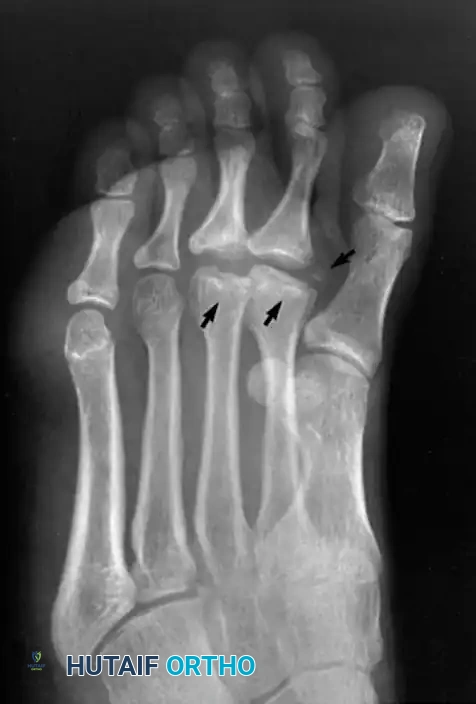

Weight-bearing anteroposterior (AP), lateral, and oblique radiographs of the foot are mandatory. Early radiographic findings may be subtle, showing only joint space widening due to effusion. As the disease progresses, classic signs emerge:

* Irregular ossification of the primary ossification center.

* Flattening and central depression of the metatarsal head.

* Widening and bicortical thickening of the metatarsal shaft.

* Osteochondral fragmentation and intra-articular loose bodies.